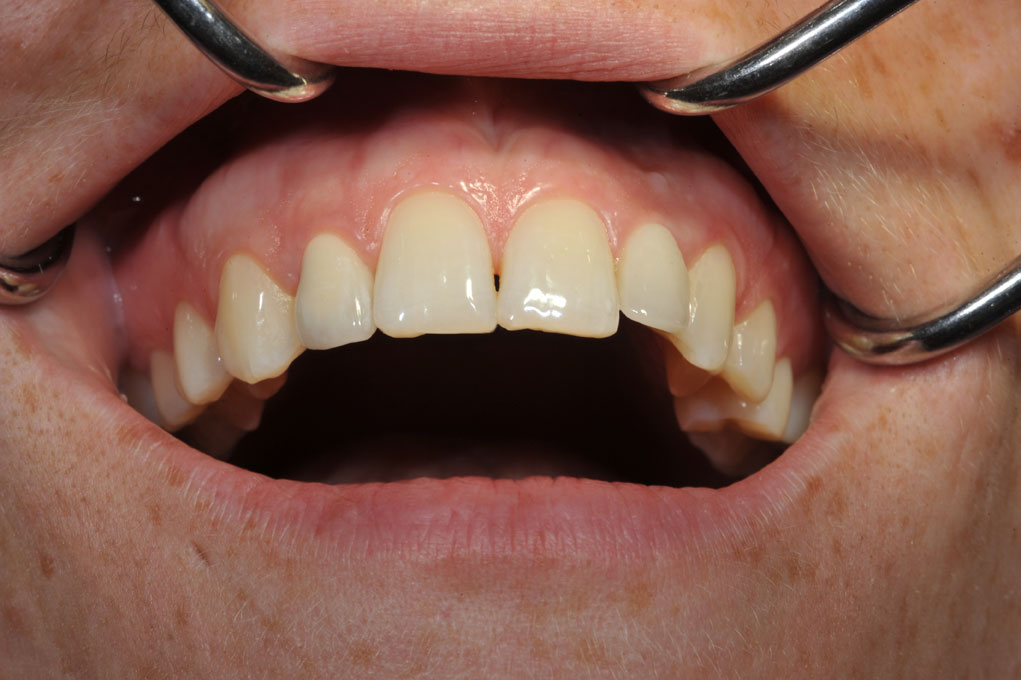

Zustand 9,5 Jahre nach Implantation